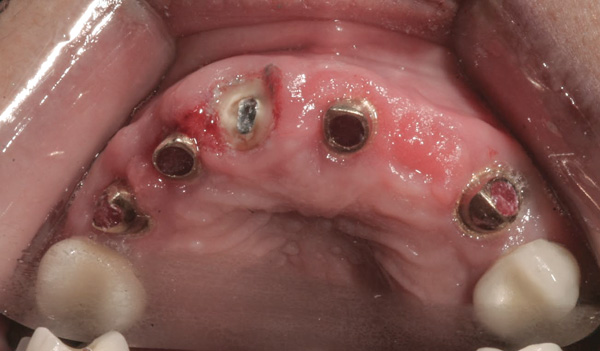

Background: This patient had a failing maxillary dentition and refused to wear a removable prosthesis. A staged approach was employed to retain some of his natural tooth abutments, and recession was noticed at the time of the impression for the second group of implants. Figure 1 shows the patient following insertion of the first set of implant custom abutments; the adjacent natural teeth are still present to support the provisional bridge. Seven months later, as shown in Figure 2, those first-stage custom abutments exhibited evidence of 1 mm to 3 mm of recession.

Figure 1 Patient following insertion of first set of implant custom abutments.

Figure 1